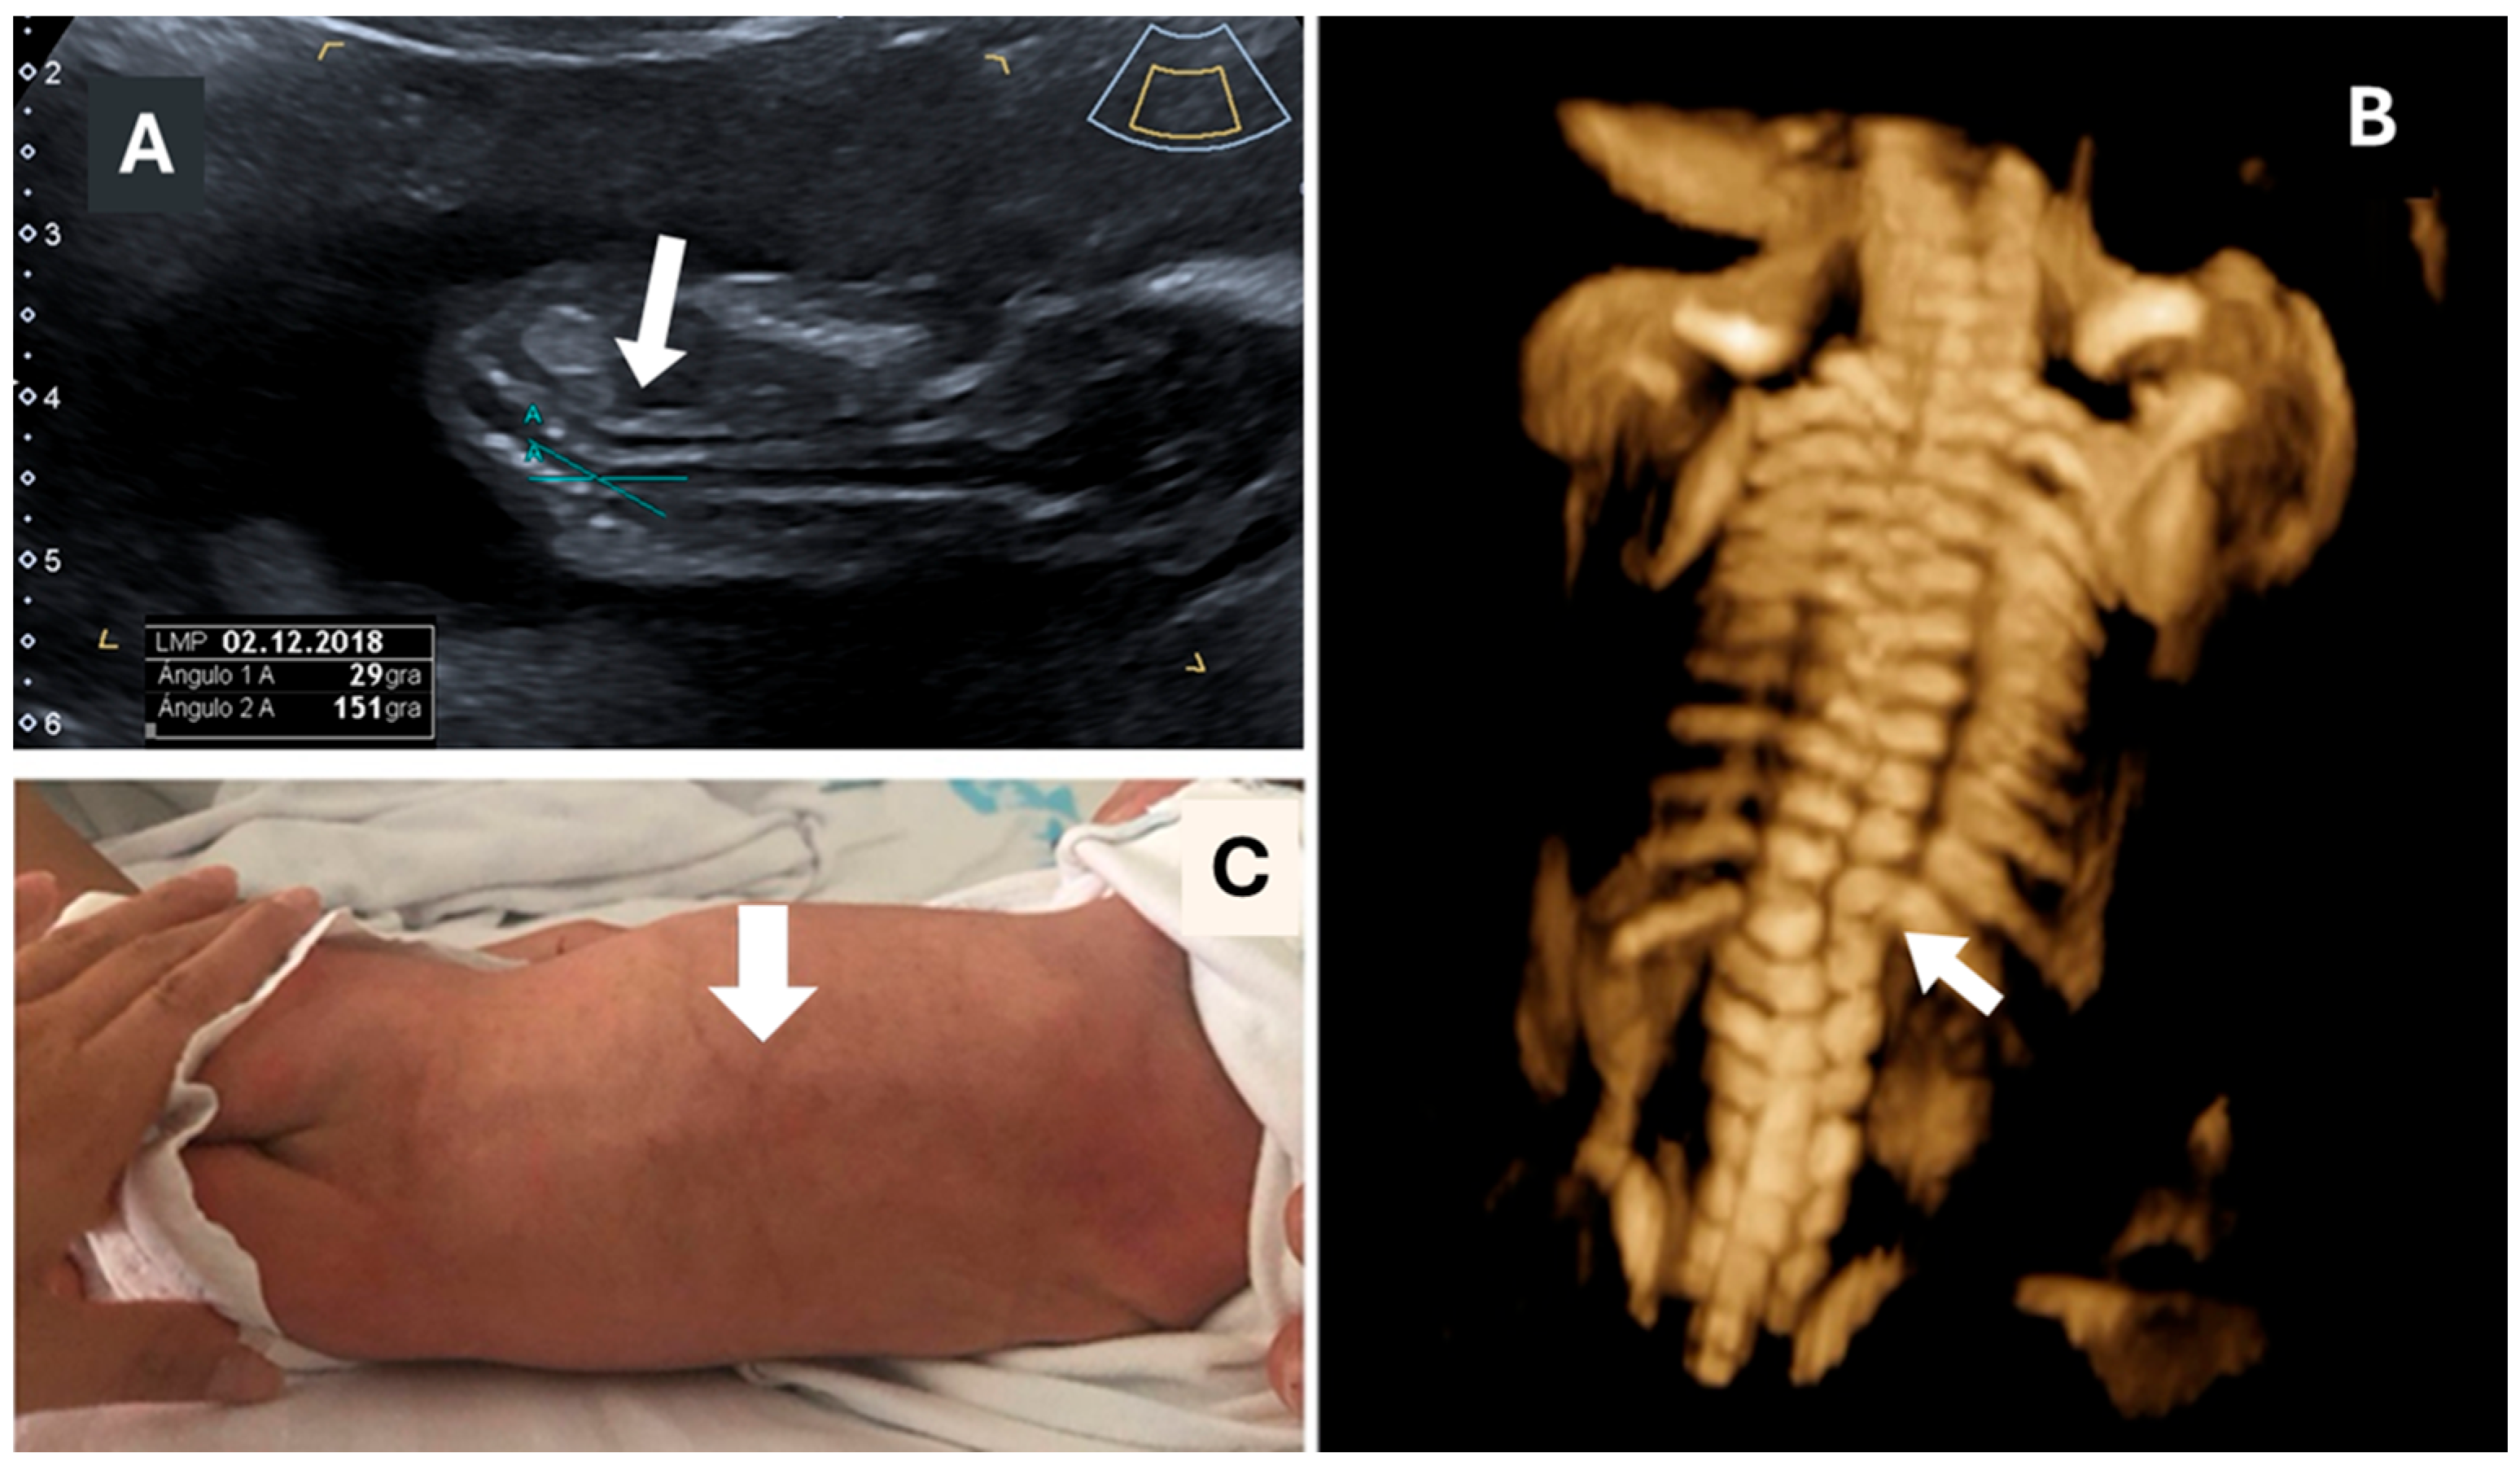

- Volpe, N.; Migliavacca, C.; Dall’Asta, A.; Kaihura, C.T.; Ghi, T.; Frusca, T. Prenatal Diagnosis of Fetal Multiple Hemivertebrae: The Importance of 3D Ultrasound Assessment. J. Matern. Neonatal Med. 2020, 33, 1755–1757. [Google Scholar] [CrossRef] [PubMed]

- Wen, Y.; Xiang, G.; Liang, X.; Tong, X. The Clinical Value of Prenatal 3D Ultrasonic Diagnosis on Fetus Hemivertebra Deformity- A Preliminary Study. Curr. Med. Imaging Rev. 2018, 14, 139–142. [Google Scholar] [CrossRef] [PubMed]

- Kalache, K.D.; Bamberg, C.; Proquitté, H.; Sarioglu, N.; Lebek, H.; Esser, T. Three-Dimensional Multi-Slice View: New Prospects for Evaluation of Congenital Anomalies in the Fetus. J. Ultrasound Med. 2006, 25, 1041–1049. [Google Scholar] [CrossRef] [PubMed]